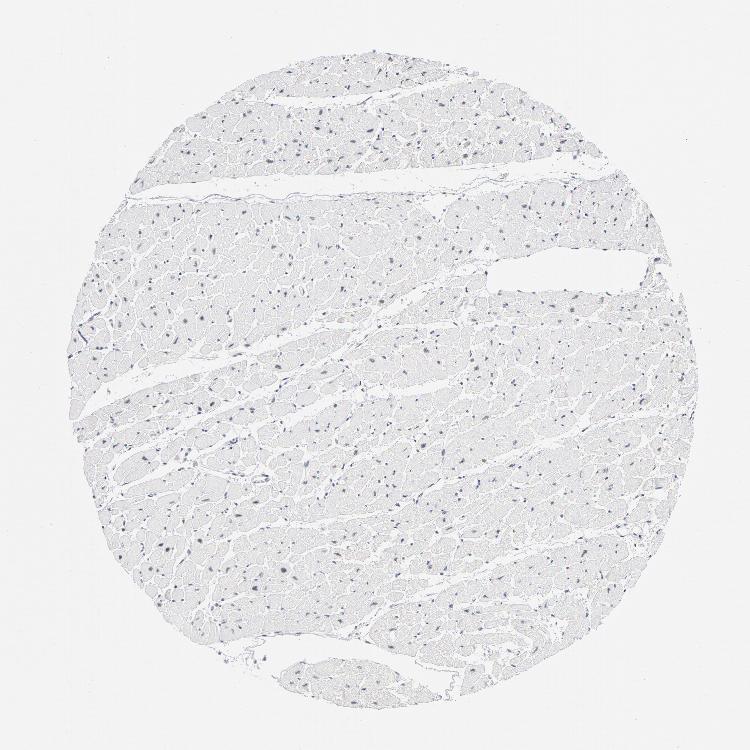

TISSUE PRIMARY DATA HEART MUSCLE Show tissue menu

Heart muscle

Heart

HEART MUSCLE - Expression summary

Protein expression

Heart musclei

On the top, protein expression in current human tissue, based on all annotated cell types, is reported with the units not detected (n), low (l), medium (m) and high (h). Underneath, protein expression in each annotated cell type are reported using the same units.

Protein expression data is based on knowledge-based annotation. For genes where more than one antibody has been used, a collective score is set.

If knowledge-based annotation could not be performed for a gene, no data is displayed here. View antibody staining data further down this page.

Cardiomyocytes: Low

HEART MUSCLE - Antibody stainingi

Antibody staining in the annotated cell types in the current human tissue is reported as not detected, low, medium, or high, based on conventional immunohistochemistry profiling in selected tissues. This score is based on the combination of the staining intensity and fraction of stained cells.

Each image is clickable and will lead to virtual microscopy that enables deeper exploration of all samples and also displays staining intensity scores, fraction scores and subcellular localization as well as patient and tissue information for each sample.

Antibody HPA049123Antibody HPA058507Antibody CAB004557

Cardiomyocytes HighNot detectedNot detected